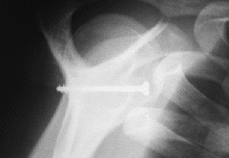

Ninguno de los pacientes intervenidos presentó nuevas luxaciones después de la cirugía. El déficit medio de rotación externa comparando las dos extremidades fue de 9° (* = 6°) y no hubo diferencias significativas en cuanto a rotación interna y la antepulsión. Un 60% de las pastillas estaban en el tercio inferior, el 20% en el tercio medio y otro 20% en el superior (Fig. 1). El 39% estaban enrasadas con el margen anterior de la glena, el 22% se habían colocado externas (Fig. 2) y el 39% se encontraban en situación demasiado medial (Fig. 3). En tan solo uno de los casos se utilizaron dos tornillos para fijar la pastilla ósea. En el resto se utilizó un tornillo pero sólo en la mitad de los casos éste atravesaba las dos corticales (Fig. 4). El tipo de tornillo más utilizado fue el maleolar (n = 18), y en tres casos se implantó un tornillo de escafoides. La mitad de las pastillas mostraban signos de consolidación, mientras que en el resto, el 21% habían migrado (Fig. 5) y el 28% se mantenían en posición merced a una unión fibrosa (Fig. 6). En ningún caso se evidenció osteolisis de la pastilla. Tan solo dos pacientes cumplían todos los parámetros radiográficos ideales. Ningún paciente requirió ser reintervenido por complicaciones clínicas posteriores, o por migración o rotura del tornillo. No se detectaron lesiones vasculonerviosas ni infección postoperatoria en ningún paciente.

Figura 5. Proyección de outlet. Migración de la pastilla ósea (flecha) e implante en el tercio superior de la glena.